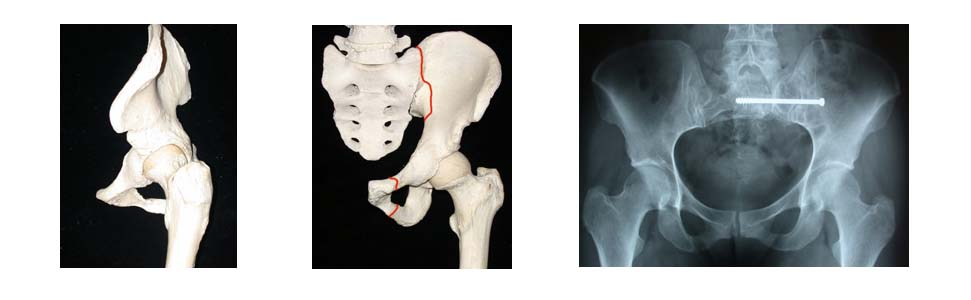

Il bacino è il più grande osso del corpo umano. In effetti il bacino è costituito da due ossa simmetriche che sono legate da una cartilagine: la sinfisi pubica.

L’emibacino è costituito da tre ossa che si saldano all’età di 12-14 anni: l’ilion, l’ischion e il pube. Il bacino è il legame meccanico tra la colonna vertebrale e gli arti inferiori.

La colonna vertebrale è incastrata tra le due ossa iliache a livello del sacro. L’articolazione corrispondente è la sacro-iliaca e l’articolazione del bacino, o la giuntura del bacino con la coscia, è l’anca.